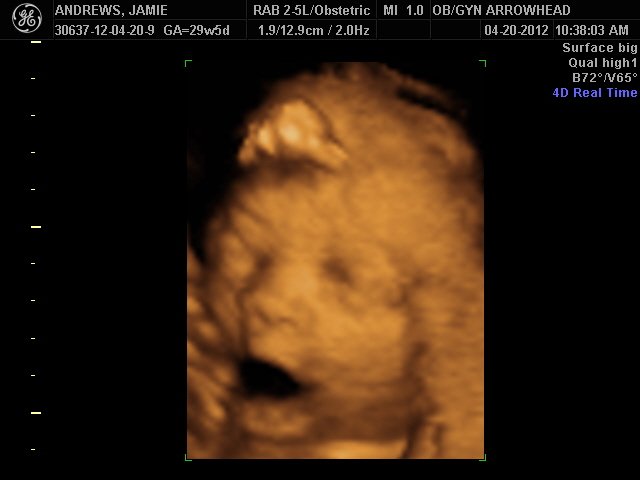

We offer complimentary 3D/4D Ultrasounds to all our OB patients around 30 weeks! The following photos are some examples of our work, shown with permission from our patients.